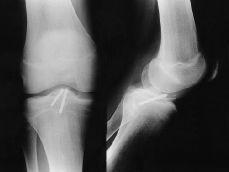

Las fracturas Tipo II, en las que no se consigue una reducción anatómica, deben tratarse quirúrgicamente mediante reducción y osteosíntesis.12,40 Todas las fracturas Tipos III, IV y V deben tratarse mediante reducción quirúrgica y osteosíntesis, habitualmente por artroscopia, empleando suturas, agujas o tornillos, recomendando una inmovilización postoperatoria de 3 semanas y descarga de 6 semanas (Fig. 1). No se recomienda la fijación transepifisaria debido al riesgo de provocar una lesión de la placa fisaria y una deformidad posterior en hiperextensión de la rodilla; para evitarlo algunos autores han recomendado realizar la sutura del fragmento al cuerno anterior del menisco medial o lateral.65

Figura 1. Niño de 14 años de edad con fractura de la espina tibial (Meyers y McKeever Grado III). A: Radiografías preoperatorias. B: Fijación artroscópica con dos tornillos de Whipple. C: Radiografía a las 10 semanas de evolución donde se aprecia consolidación de la fractura.